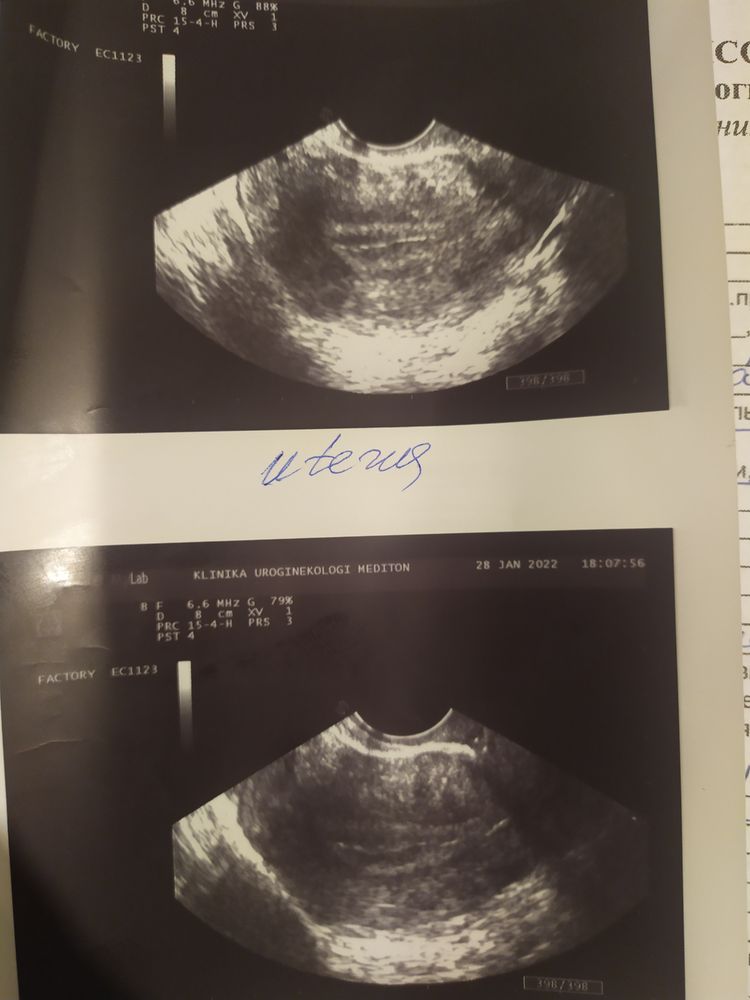

На графике О выставила сама,график мне ставил раньше,я тесты на Б делала,они были чистые,а БТ не падала,я и подумала что О позже.Тесты начала делать на 14 ДПО,сразу были видны полоски,БТ не падала.Но сегодня упала.Появилось совсем немного выделений красных.Я сразу пошла на приём и УЗИ.

На УЗИ естественно ничего не обнаружили+врач сказала,что Б и не пахнет....ЖТ с левой стороны,где у меня нет трубы....На фото тест позавчера вечер и сегодня вечер,особо не поярчал... Тянет левый яичник,после осмотра,и опять немного выделений.